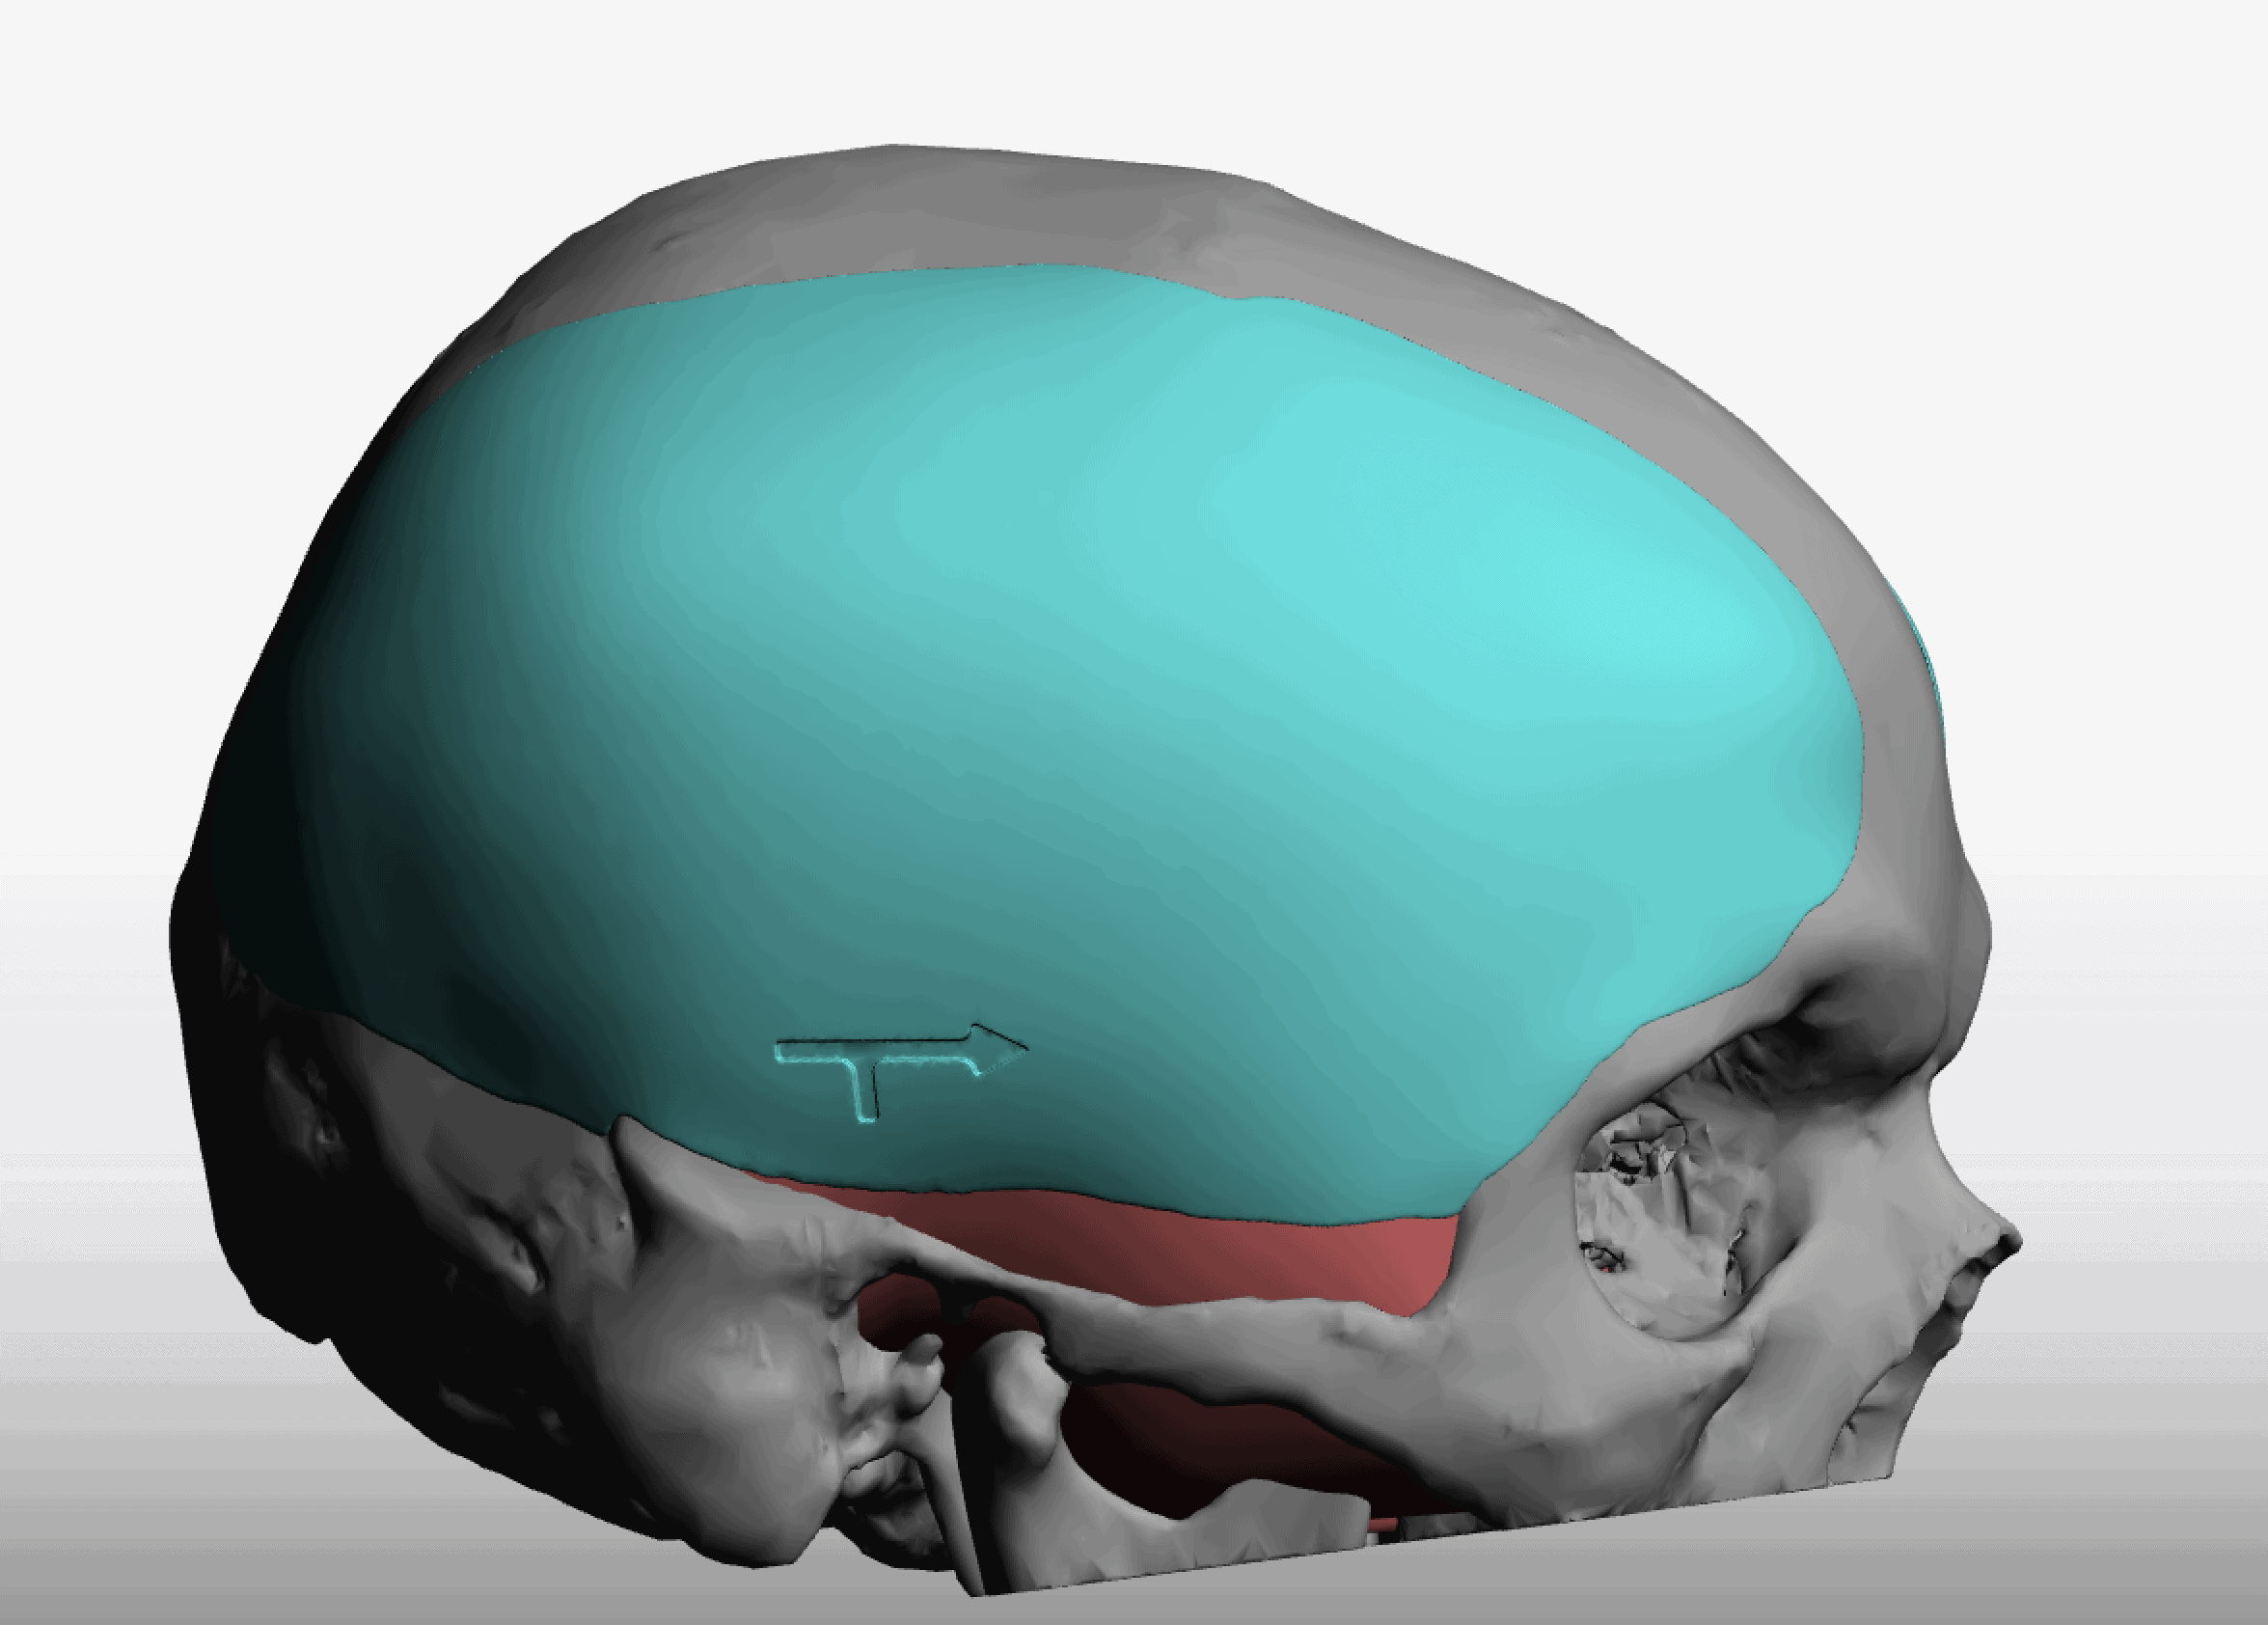

Desire for change of head shape from front view form an inverted V shape to a rounder and wider head shape.

Placement of custom extended forehead-temporal implants through incisions in the crease behind the ear. (he had a prior back of head skull implant which is green in the implant designs and which the head widening implants partially covered it)

Desire for change of head shape from front view form an inverted V shape to a rounder and wider head shape.

Placement of custom extended forehead-temporal implants through incisions in the crease behind the ear. (he had a prior back of head skull implant which is green in the implant designs and which the head widening implants partially covered it)